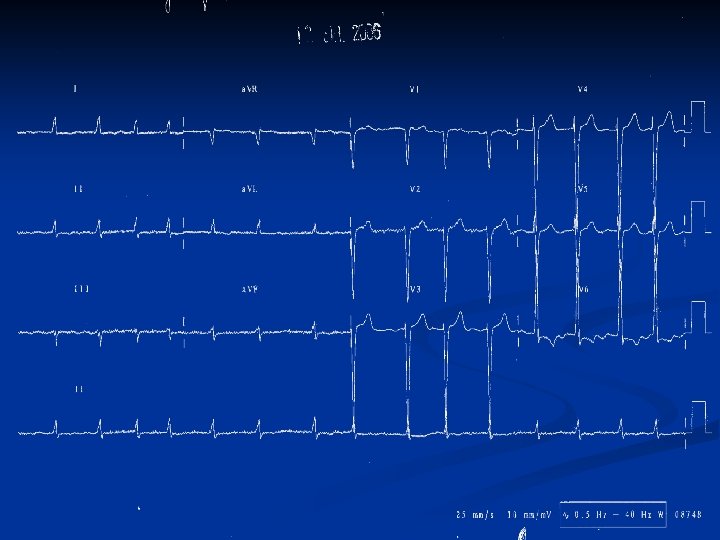

Lab tests + other exams n Lung functions test: mild restriction n EKG: atrial fibrilation, 110/min, horizontal axis deviation, TZ V 4, V 5, voltage criteria for LV hypertrophy with signs of LV obverload, no fresh ischemic changes